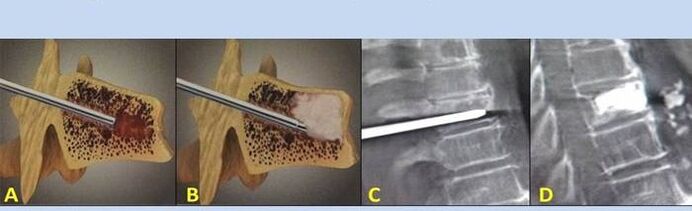

- Nucleoplasty– removal of the core of the intervertebral disc.The operation relieves the pressure on the nerve endings.

- Puncture vertebroplasty– a method of stabilizing the vertebrae.During the procedure, the doctor fills the spinal cavities with bone cement.